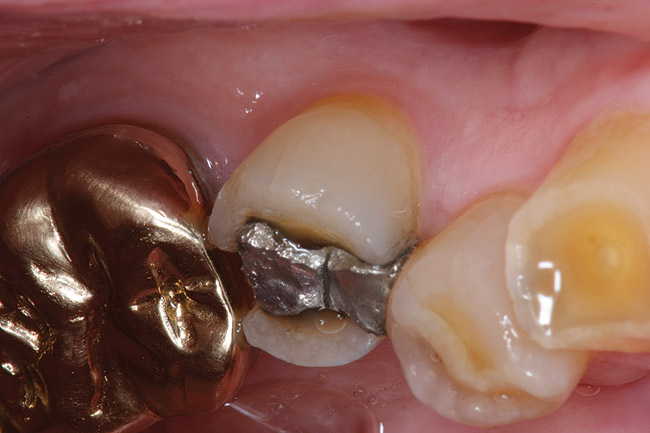

Replacement of existing restorations is responsible for 75% of all operative dentistry.15,19 The reasons for placement and replacement of restorations of direct restorative materials include: primary caries (Figure 1 and Figure 2); recurrent caries (Figure 3); poor margins (Figure 4 and Figure 5); restoration fracture (Figure 6 and Figure 7); tooth fracture (Figure 8); esthetics (Figure 9); non-carious tooth structure lost (attrition, abrasion, abfraction, erosion) (Figure 10); and pain/sensitivity.

Fig. 3 Maxillary first molar with mesiobuccal tooth fracture and recurrent caries.

Figure 3  Maxillary first molar with mesiobuccal tooth fracture and recurrent caries.

Figure 3